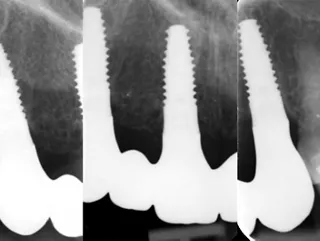

• Radiographie périapicale lors du suivi à 6 mois